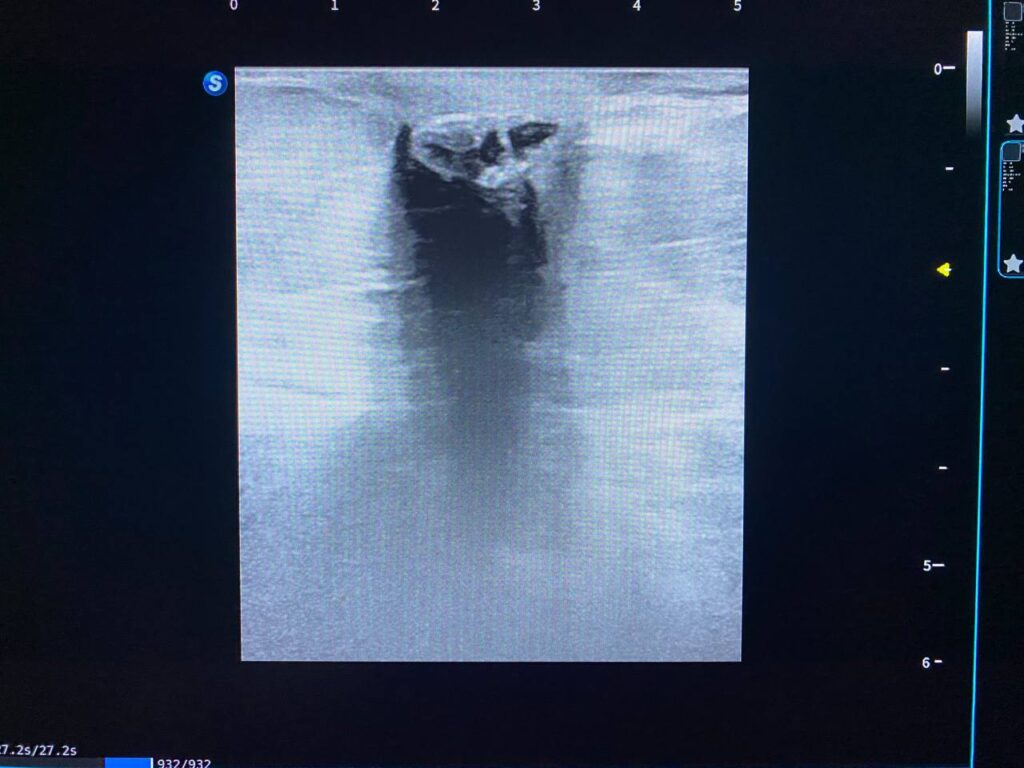

Findings: Left breast: UOQ ,scar tissue+ presence of heterogenous calcified mass 5.3×8.1mm, under the skin , mostly calcified hematoma ,no suspicious solid mass, nor collection seen at the bed, nor at the other part of the breast

Findings: Left breast: UOQ ,scar tissue+ presence of heterogenous calcified mass 5.3×8.1mm, under the skin , mostly calcified hematoma ,no suspicious solid mass, nor collection seen at the bed, nor at the other part of the breast